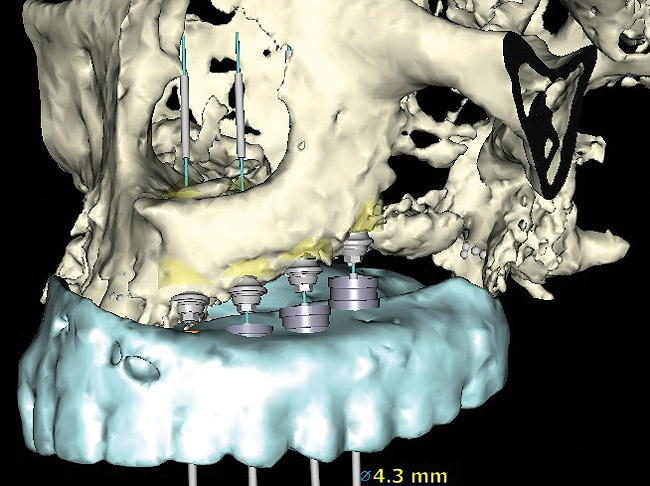

Figure 2  Surgical guide with implants placed attached to implant mounts, three implants in row. Note implant spacing and varying implant diameters corresponding to individual site’s planned dental restorations.

Figure 2

When three or more implants in a row are planned, concepts of spacing and angulations, parallelism in all dimensions, proximity to anatomic structures, and relationships between implant positions and planned restorations are all significant considerations. CT/CBCT-guided surgery allows for the ideal placement of multiple dental implants according to the planned restoration while taking these issues into consideration (Figure 2 and Figure 3). Implants can be placed flaplessly and immediately loaded.6-8,11-14,25-29